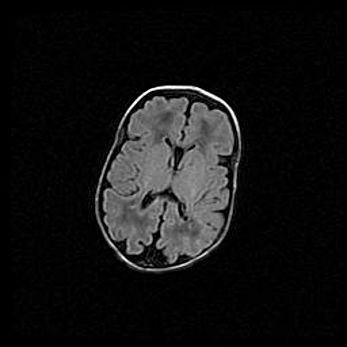

Лейкомаляция с кистозно-глиозной дегенерацией головного мозга.

Возраст: 2 месяца 25 дней

Вес: 6400 г

Окружность головы: 40 см

Срок гестации: 41 неделя

Лейкомаляцию относят к ишемически-гипоксическим повреждениям головного мозга, диагностируемым у новорожденных. При лейкомаляции в головном мозге обнаруживают очаги некроза, возникшие после тяжелой гипоксии и нарушения кровотока. В процессе морфогенеза очаги проходят три стадии: 1) развития некроза, 2) резорбции и 3) формирования глиозного рубца или кисты. Перивентрикулярная лейкомаляция (ПЛ) встречается примерно в 12% случаев среди новорожденных, обычно – у недоношенных детей, причем, частота ее зависит от массы, с которой младенец появился на свет. Наибольшее число малышей страдает лейкомаляцией, если масса при рождении 1500-2500 г.